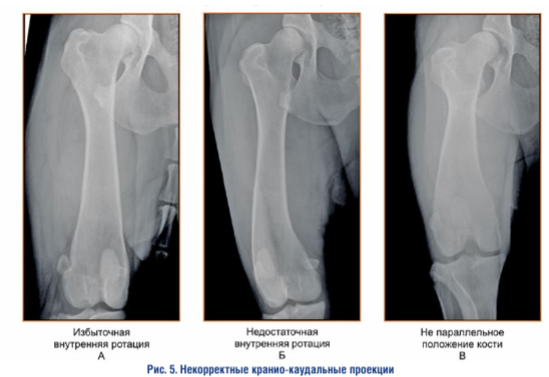

Некорректные проекции. Скошенная форма межмыщелковой ямки с заостренной вершиной служит свидетельством «косого» положения дистального эпифиза бедренной кости относительно фронтальной плоскости.

Смещение заостренной вершины межмыщелковой ямки в медиальную сторону свидетельствует об излишней внутренней ротации бедренной кости.

Смещение заостренной вершины межмыщелковой ямки в латеральную сторону свидетельствует об излишней внешней ротации бедренной кости.

При отсутствии вывиха коленной чашки ее положение, не соответствующее нейтральному положению относительно центра дистального эпифиза, служит свидетельством «косого» положения дистального эпифиза бедренной кости относительно фронтальной плоскости.

Смещение коленной чашки в медиальную сторону (при отсутствии вывиха коленной чашки) свидетельствует об излишней внутренней ротации бедренной кости.

Смещение коленной чашки в латеральную сторону (при отсутствии вывиха коленной чашки) свидетельствует об излишней внешней ротации бедренной кости.

Положение коленной чашки не на линии, соединяющей сесамовидные кости, служит свидетельством «не параллельного» положения бедренной кости относительно фронтальной плоскости.